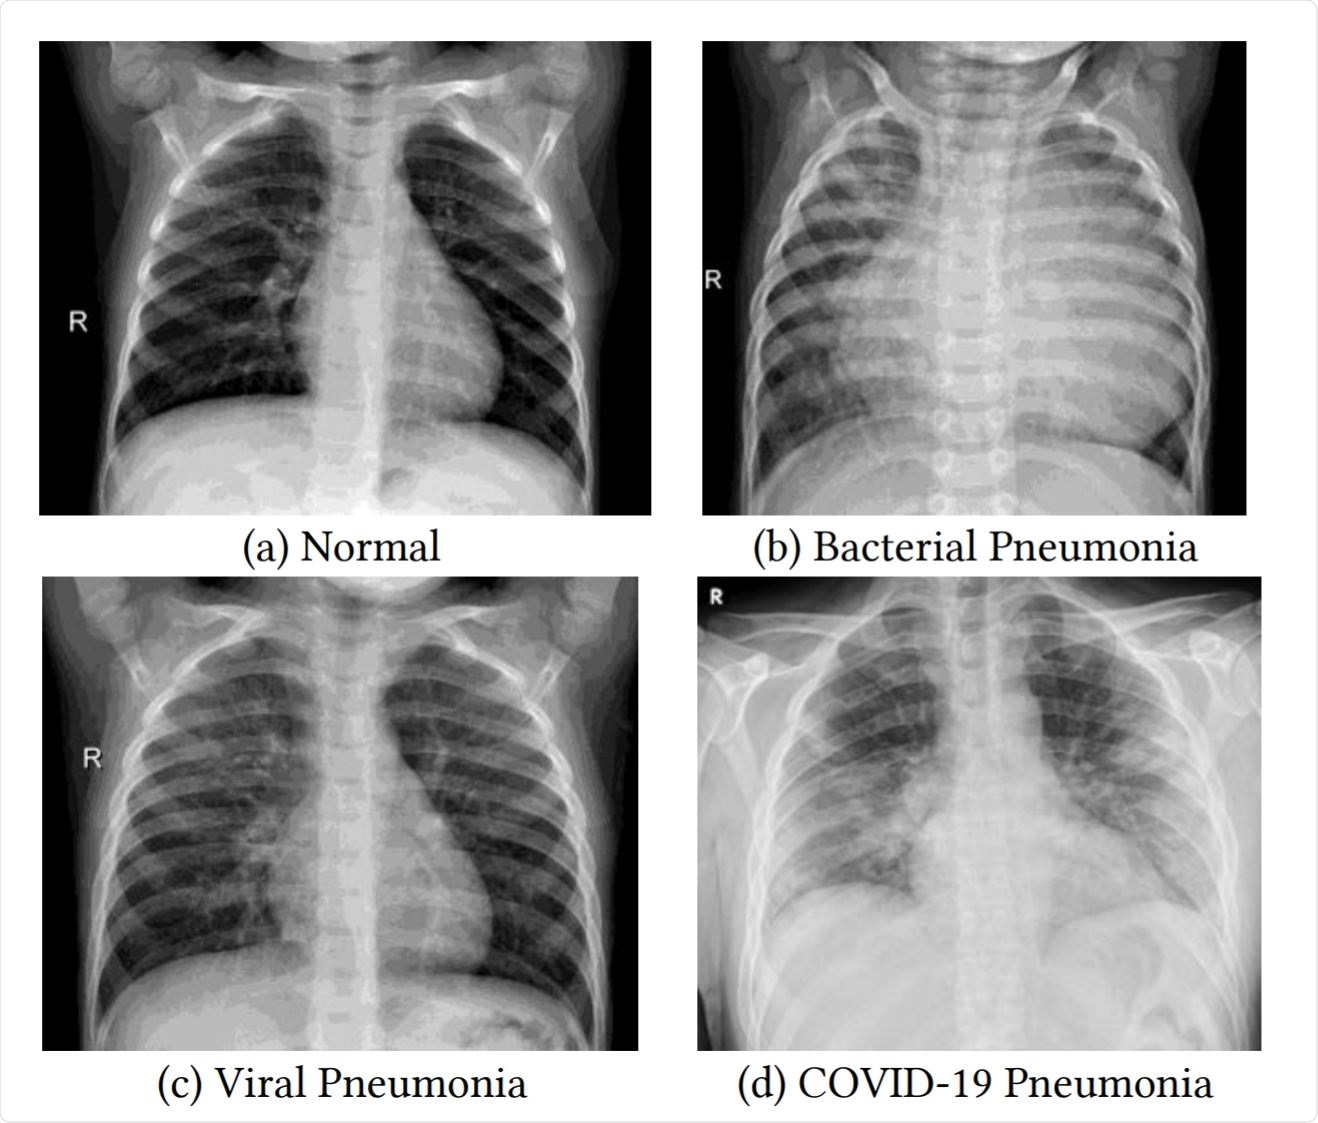

Examples of frontal-view chest X-Ray images from the datasets. Image Credit: https://www.medrxiv.org/content/10.1101/2020.12.14.20248158v1.full.pdf

COVID-19 affects the lungs, primarily, although it can damage multiple organs in severe or critical disease. Thus, chest X-rays play a large part in the diagnosis of COVID-19 pneumonia. Important findings in this condition include increased whiteness of the lungs, proportional to the severity of the disease.

The typical radiographic appearance of the lungs in COVID-19 pneumonia is of ground-glass opacities and sometimes of linear opacities in the lung periphery, with the lung markings being somewhat obscured. As the condition becomes more severe, these markings become invisible, or ‘whited-out’.